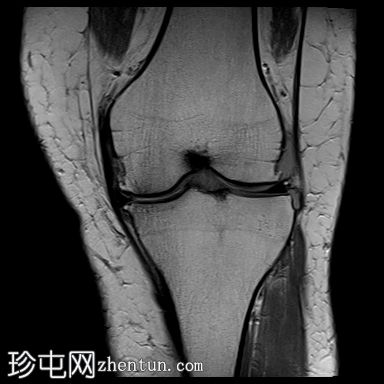

冠状位质子密度加权像 (PD)

脂肪抑制像

前交叉韧带 (ACL) 呈增厚的高信号,提示黏液样变性。然而,纤维仍保持连续性,在矢状位质子密度加权像上尤为明显。这种特征性表现类似于芹菜,因此被称为“芹菜茎征”。

内侧半月板后角显示异常信号,延伸至关节面下方,符合3级撕裂。

髌股关节和胫股关节均可见骨关节炎改变,表现为骨赘形成、胫骨棘突增生以及关节软骨在相对关节面上的剥脱。

可见少量滑液积液,滑液内可见髌上皱襞。

内侧副韧带可见异常水肿信号,但未见纤维断裂,提示为I级扭伤。

此外,胫股关节胫骨髁间区可见局灶性软骨变薄,伴有骨暴露和骨髓水肿。